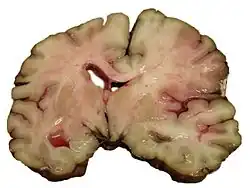

Intracerebral hemorrhage

It generally occurs in small arteries or arterioles and is commonly due to hypertension,[58] intracranial vascular malformations (including cavernous angiomas or arteriovenous malformations), cerebral amyloid angiopathy, or infarcts into which secondary hemorrhage has occurred.[2] Other potential causes are trauma, bleeding disorders, amyloid angiopathy, illicit drug use (e.g., amphetamines or cocaine). The hematoma enlarges until pressure from surrounding tissue limits its growth, or until it decompresses by emptying into the ventricular system, CSF or the pial surface. A third of intracerebral bleed is into the brain's ventricles. ICH has a mortality rate of 44 percent after 30 days, higher than ischemic stroke or subarachnoid hemorrhage (which technically may also be classified as a type of stroke[2]).